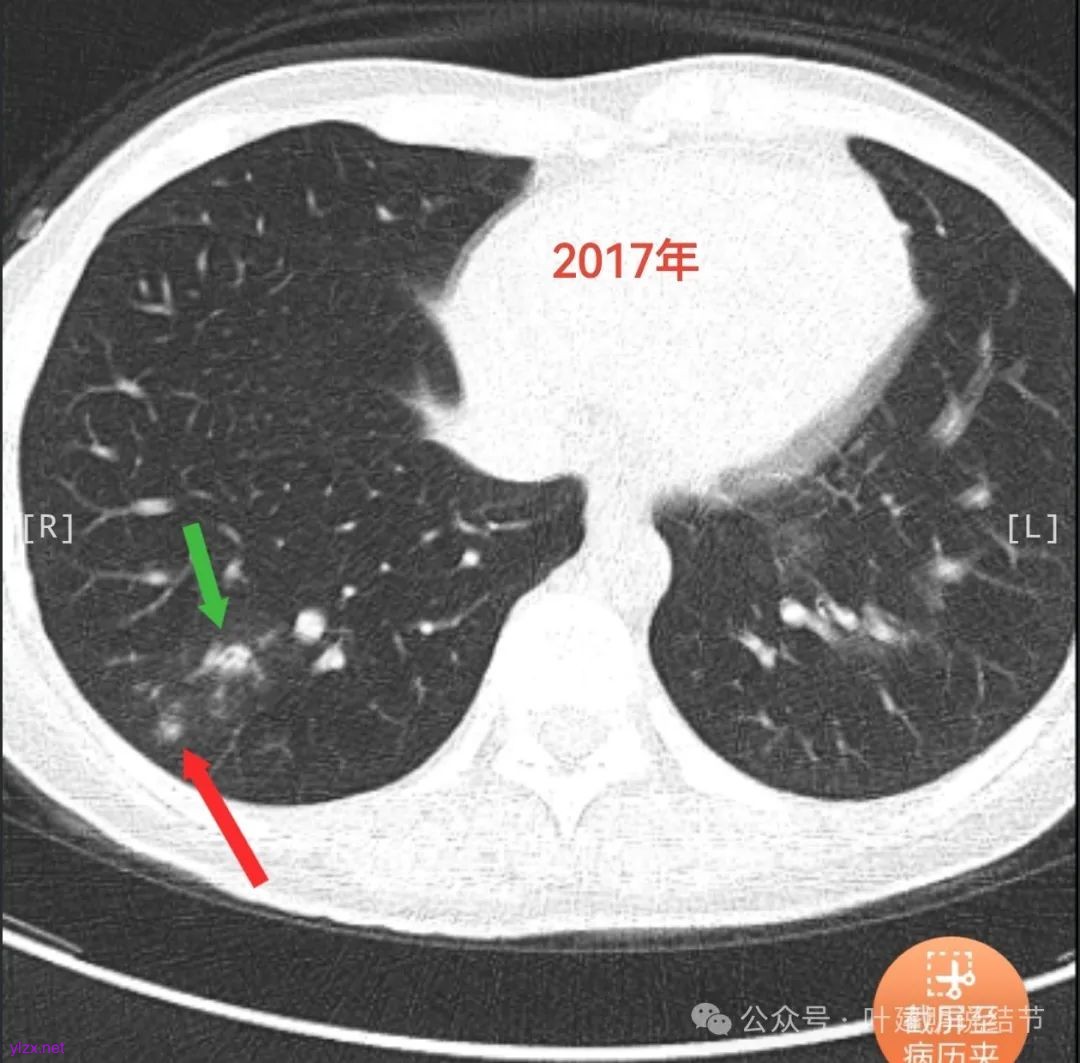

结友后来又上传了2017年时的影像:

看了2017年的影像后,我又觉得病灶与附近炎性的形态类似,而且7年来进展也不厉害,慢性炎伴纤维增生的可能性也是有的。所以先半年复查,再有进展更像恶性再手术也可以。